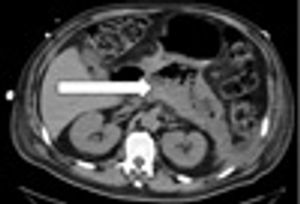

Emphysematous pancreatitis is a rare form of necrotizing pancreatitis. Free air within the pancreatic parenchyma is typically attributed to infection.